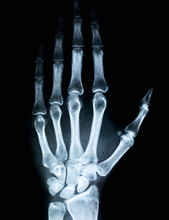

x raysLa mayoría de los estudios de rayos X no requieren una preparación extensa, pero hay ciertas pautas generales que deben seguirse para asegurar imágenes nítidas y precisas:

En el caso de radiografías de extremidades, como brazos o piernas, no suele ser necesario realizar una preparación especial más allá del retiro de objetos metálicos.